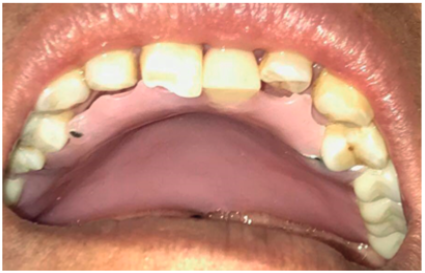

Se procedió a la restauración de todos los órganos dentarios en 4 sesiones diferentes, en las cuales se trató con éxito la necrosis pulpar y las caries en dentina; además, se colocó una placa de acrílico como medida paliativa para la fonación y la deglución (figura 2).

Figura 2. Placa de acrílico

Fuente: historia clínica del paciente

Después de la colocación de la placa de acrílico, se realizaron 24 sesiones ordinarias y 10 de refuerzo en las que se realizaron ejercicios de articulación de fonemas, enfatizando en los que la paciente mostró mayores dificultades; una vez concluidas, mejoró la producción del habla alcanzando el rango medio con resultados de 76/110 y 8/15 respectivamente según los instrumentos de evaluación mencionados.